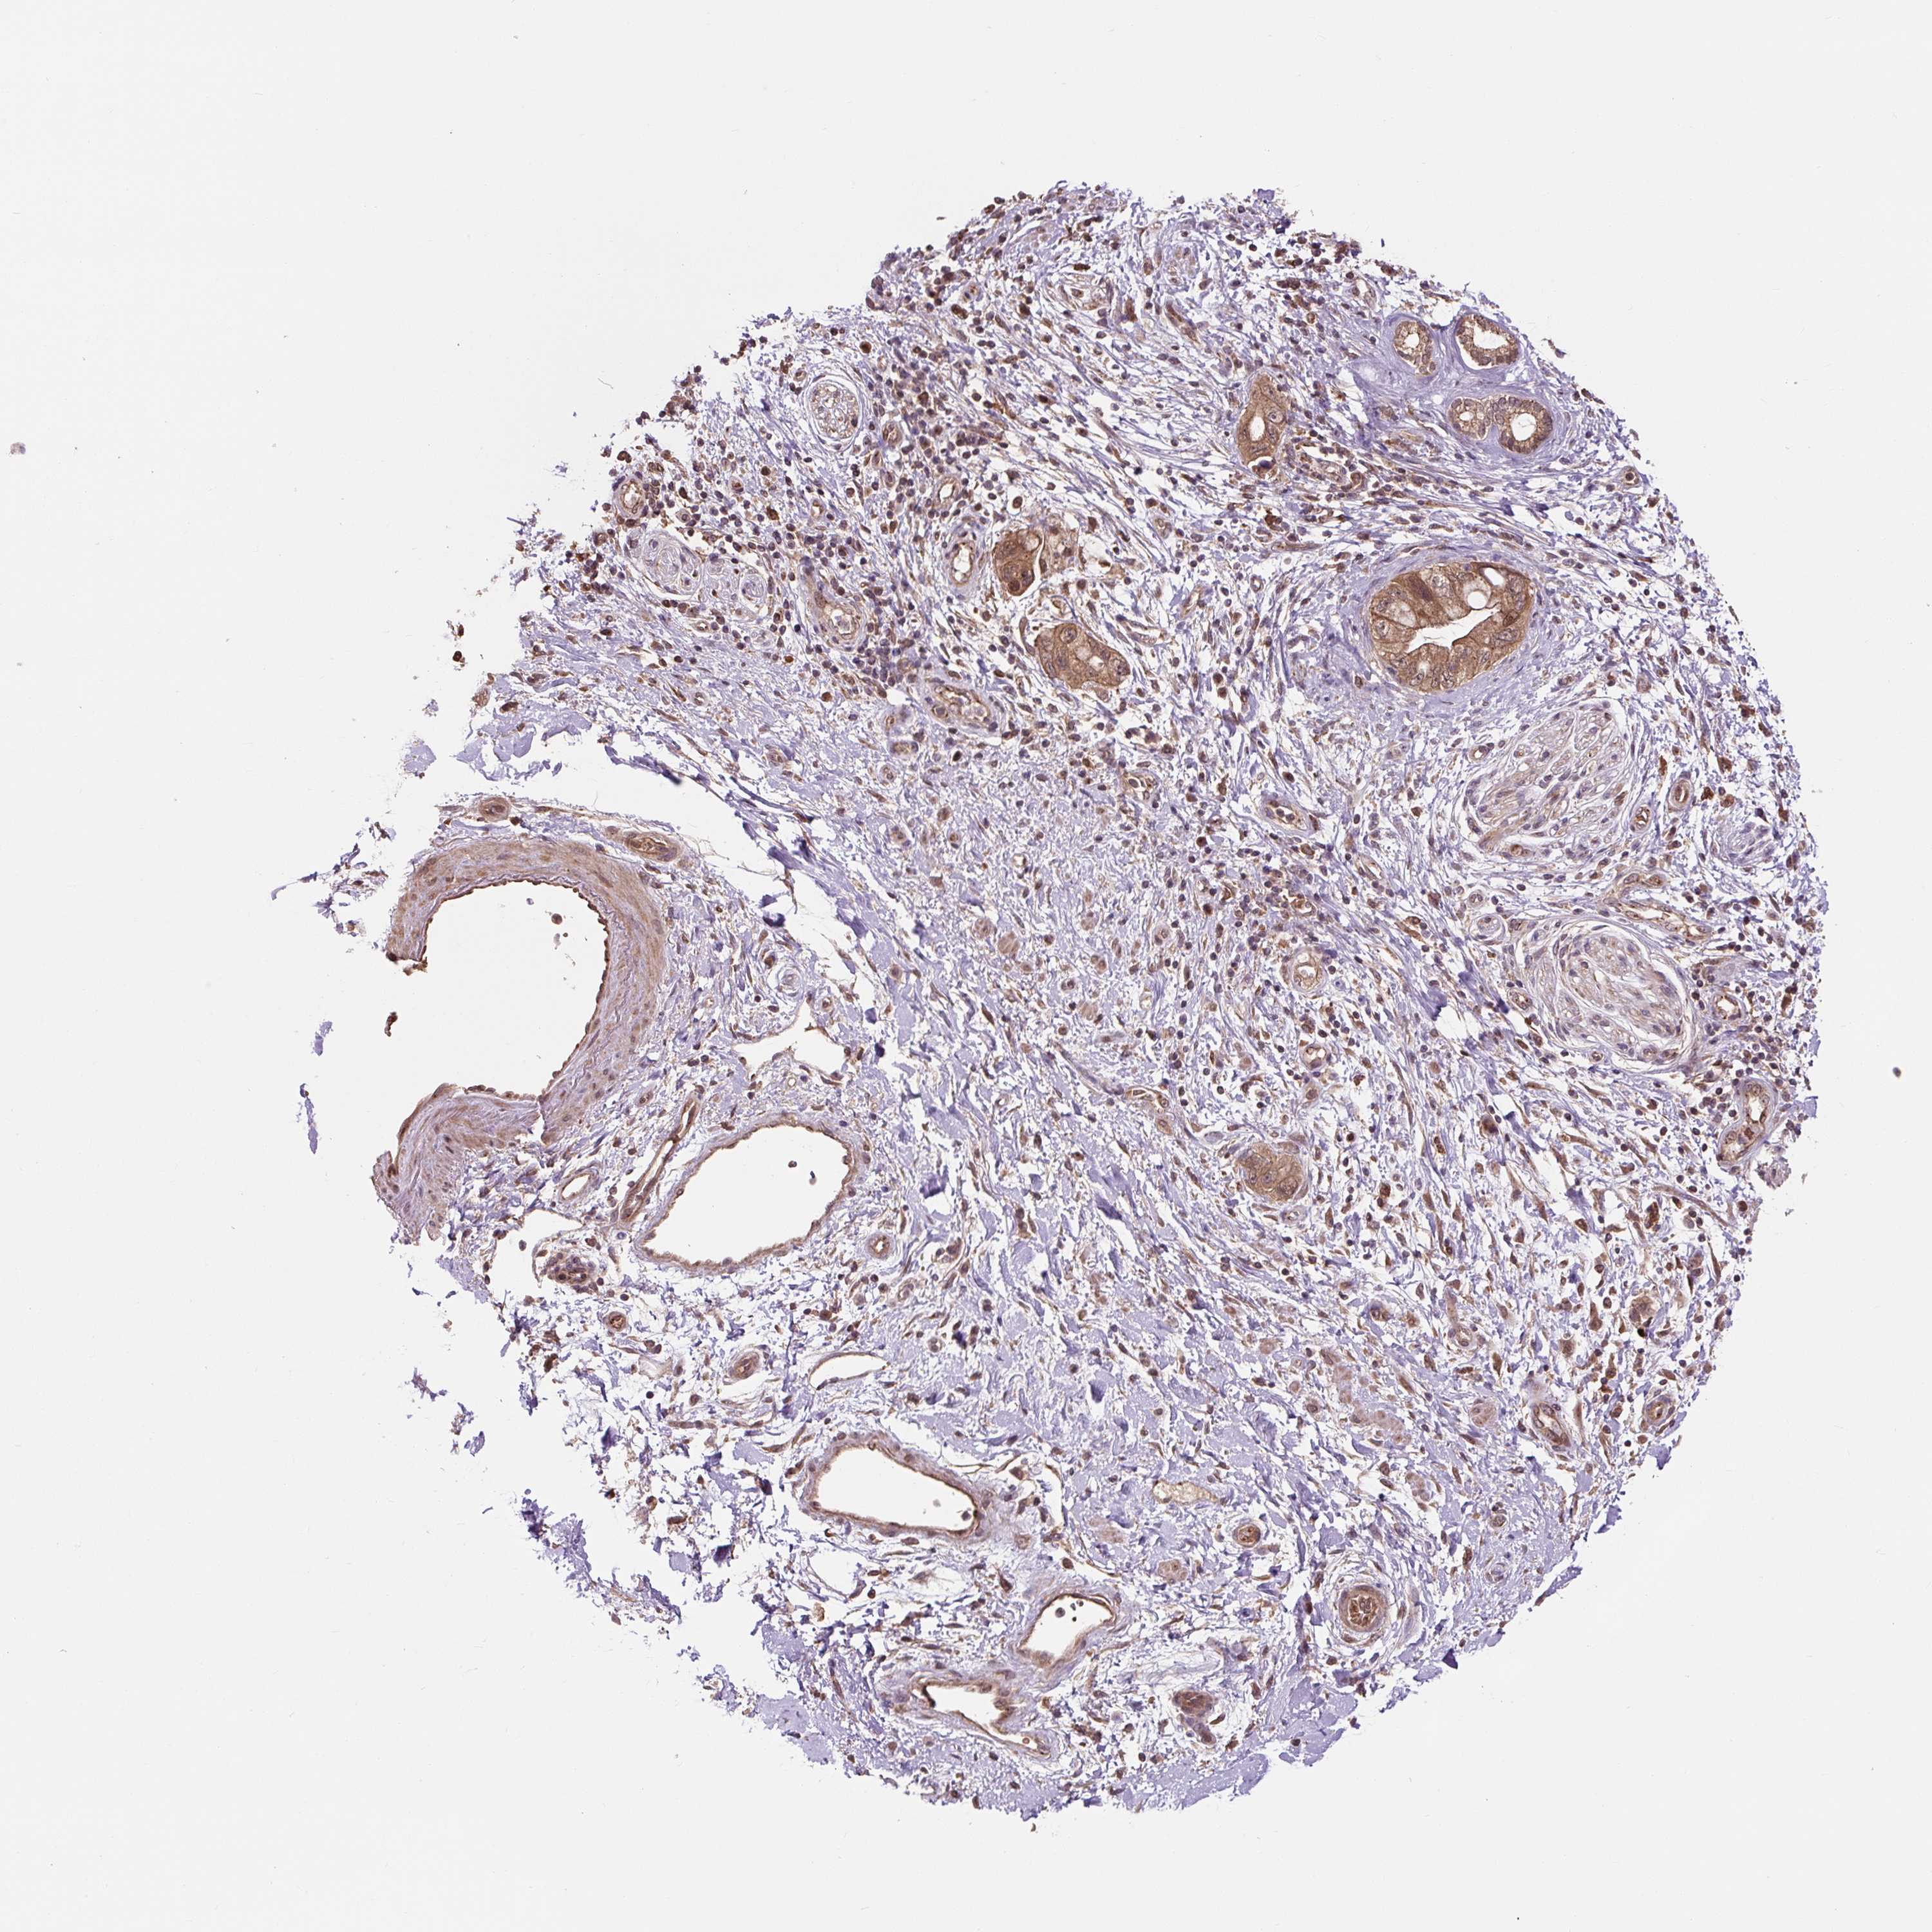

PANCREATIC CANCER - Protein expressioni

A mouse-over function shows sample information and annotation data. Click on an image to view it in a full screen mode. Samples can be filtered based on level of antibody staining by selecting one or several of the following categories: high, medium, low and not detected. The assay and annotation is described here.

Note that samples used for immunohistochemistry by the Human Protein Atlas do not correspond to samples in the TCGA dataset.

Antibody stainingi

Antibody staining in the annotated cell types in the current human tissue is reported as not detected, low, medium, or high, based on conventional immunohistochemistry profiling in selected tissues. This score is based on the combination of the staining intensity and fraction of stained cells.

Each image is clickable and will lead to virtual microscopy that enables deeper exploration of all samples and also displays staining intensity scores, fraction scores and subcellular localization as well as patient and tissue information for each sample.

Antibody HPA056299

Staining

High

Medium

Low

Not detected

Intensity

Strong

Moderate

Weak

Negative

Quantity

>75%

75%-25%

<25%

None

Location

Nuclear

Cytoplasmic/membranous

Cytoplasmic/membranous,nuclear

Adenocarcinoma, NOS